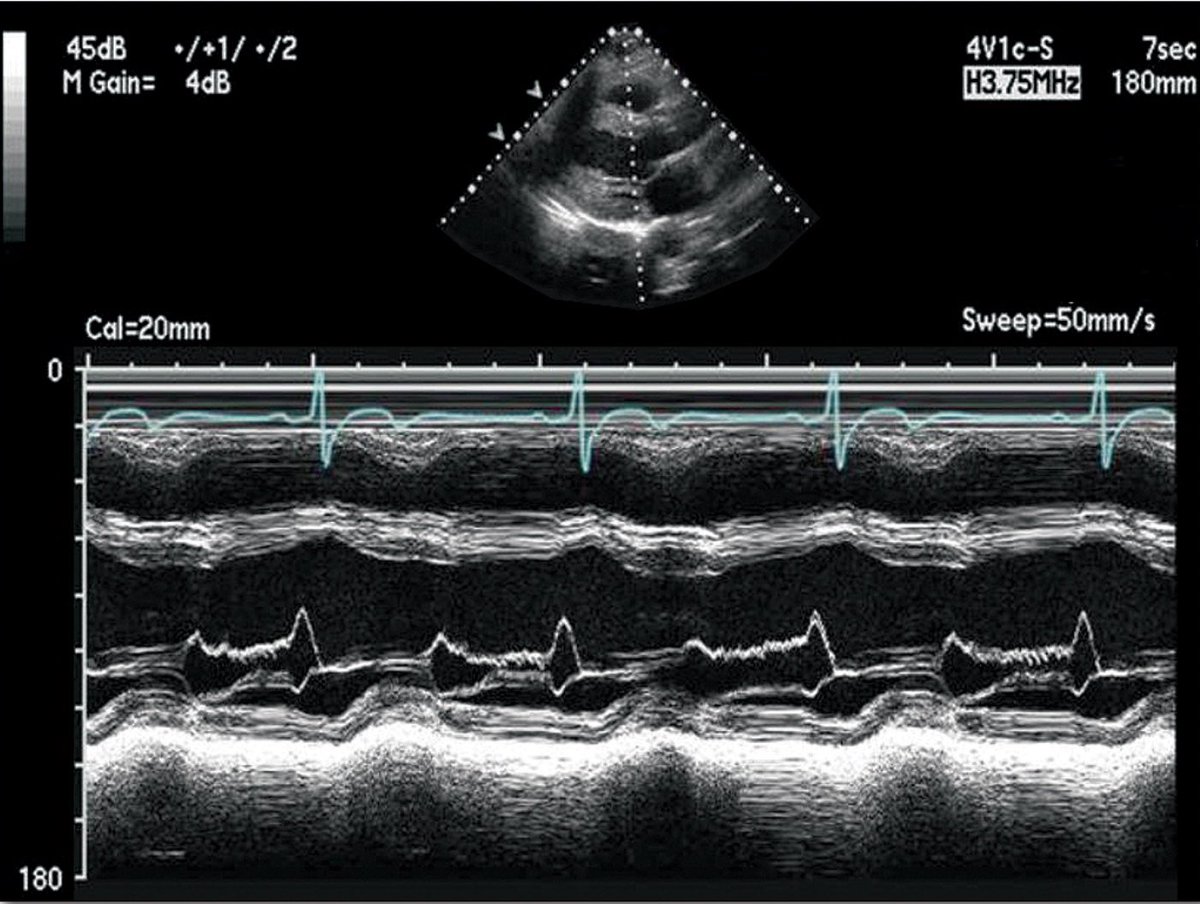

An impressive representation from our fellows at ACC24!! All under the guidance of our stellar PD @RajasekharNekkanti #ECUCards 🫀